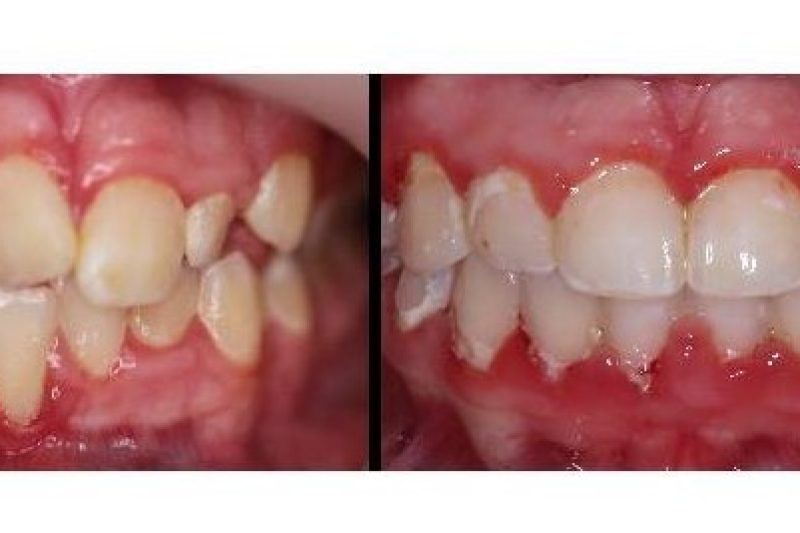

Been doing this for 19y, but I’m still amazed how my work can change a person’s look/life in just a year!